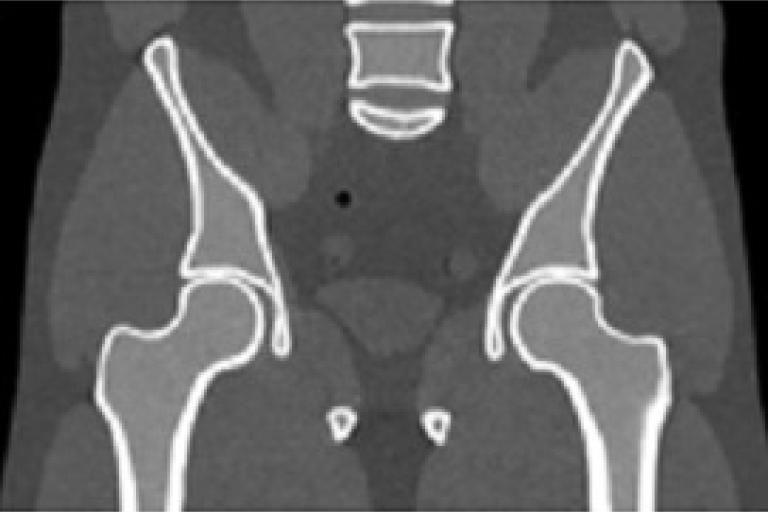

There is growing concern on the radiation dose delivered to patient during CT or cone-beam CT (CBCT) procedure, especially for pediatric patients, screening, or repeated acquisitions for CBCT-guided radiation therapy over a whole treatment course. We have developed various strategies to enhance image quality of low-dose CT and CBCT.

• Modeling the statistical properties of noise in low-dose CT/CBCT data.

• Developing and optimizing statistics-based projection restoration and iterative image reconstruction algorithms. We are currently evaluating these algorithms on clinical patient images.